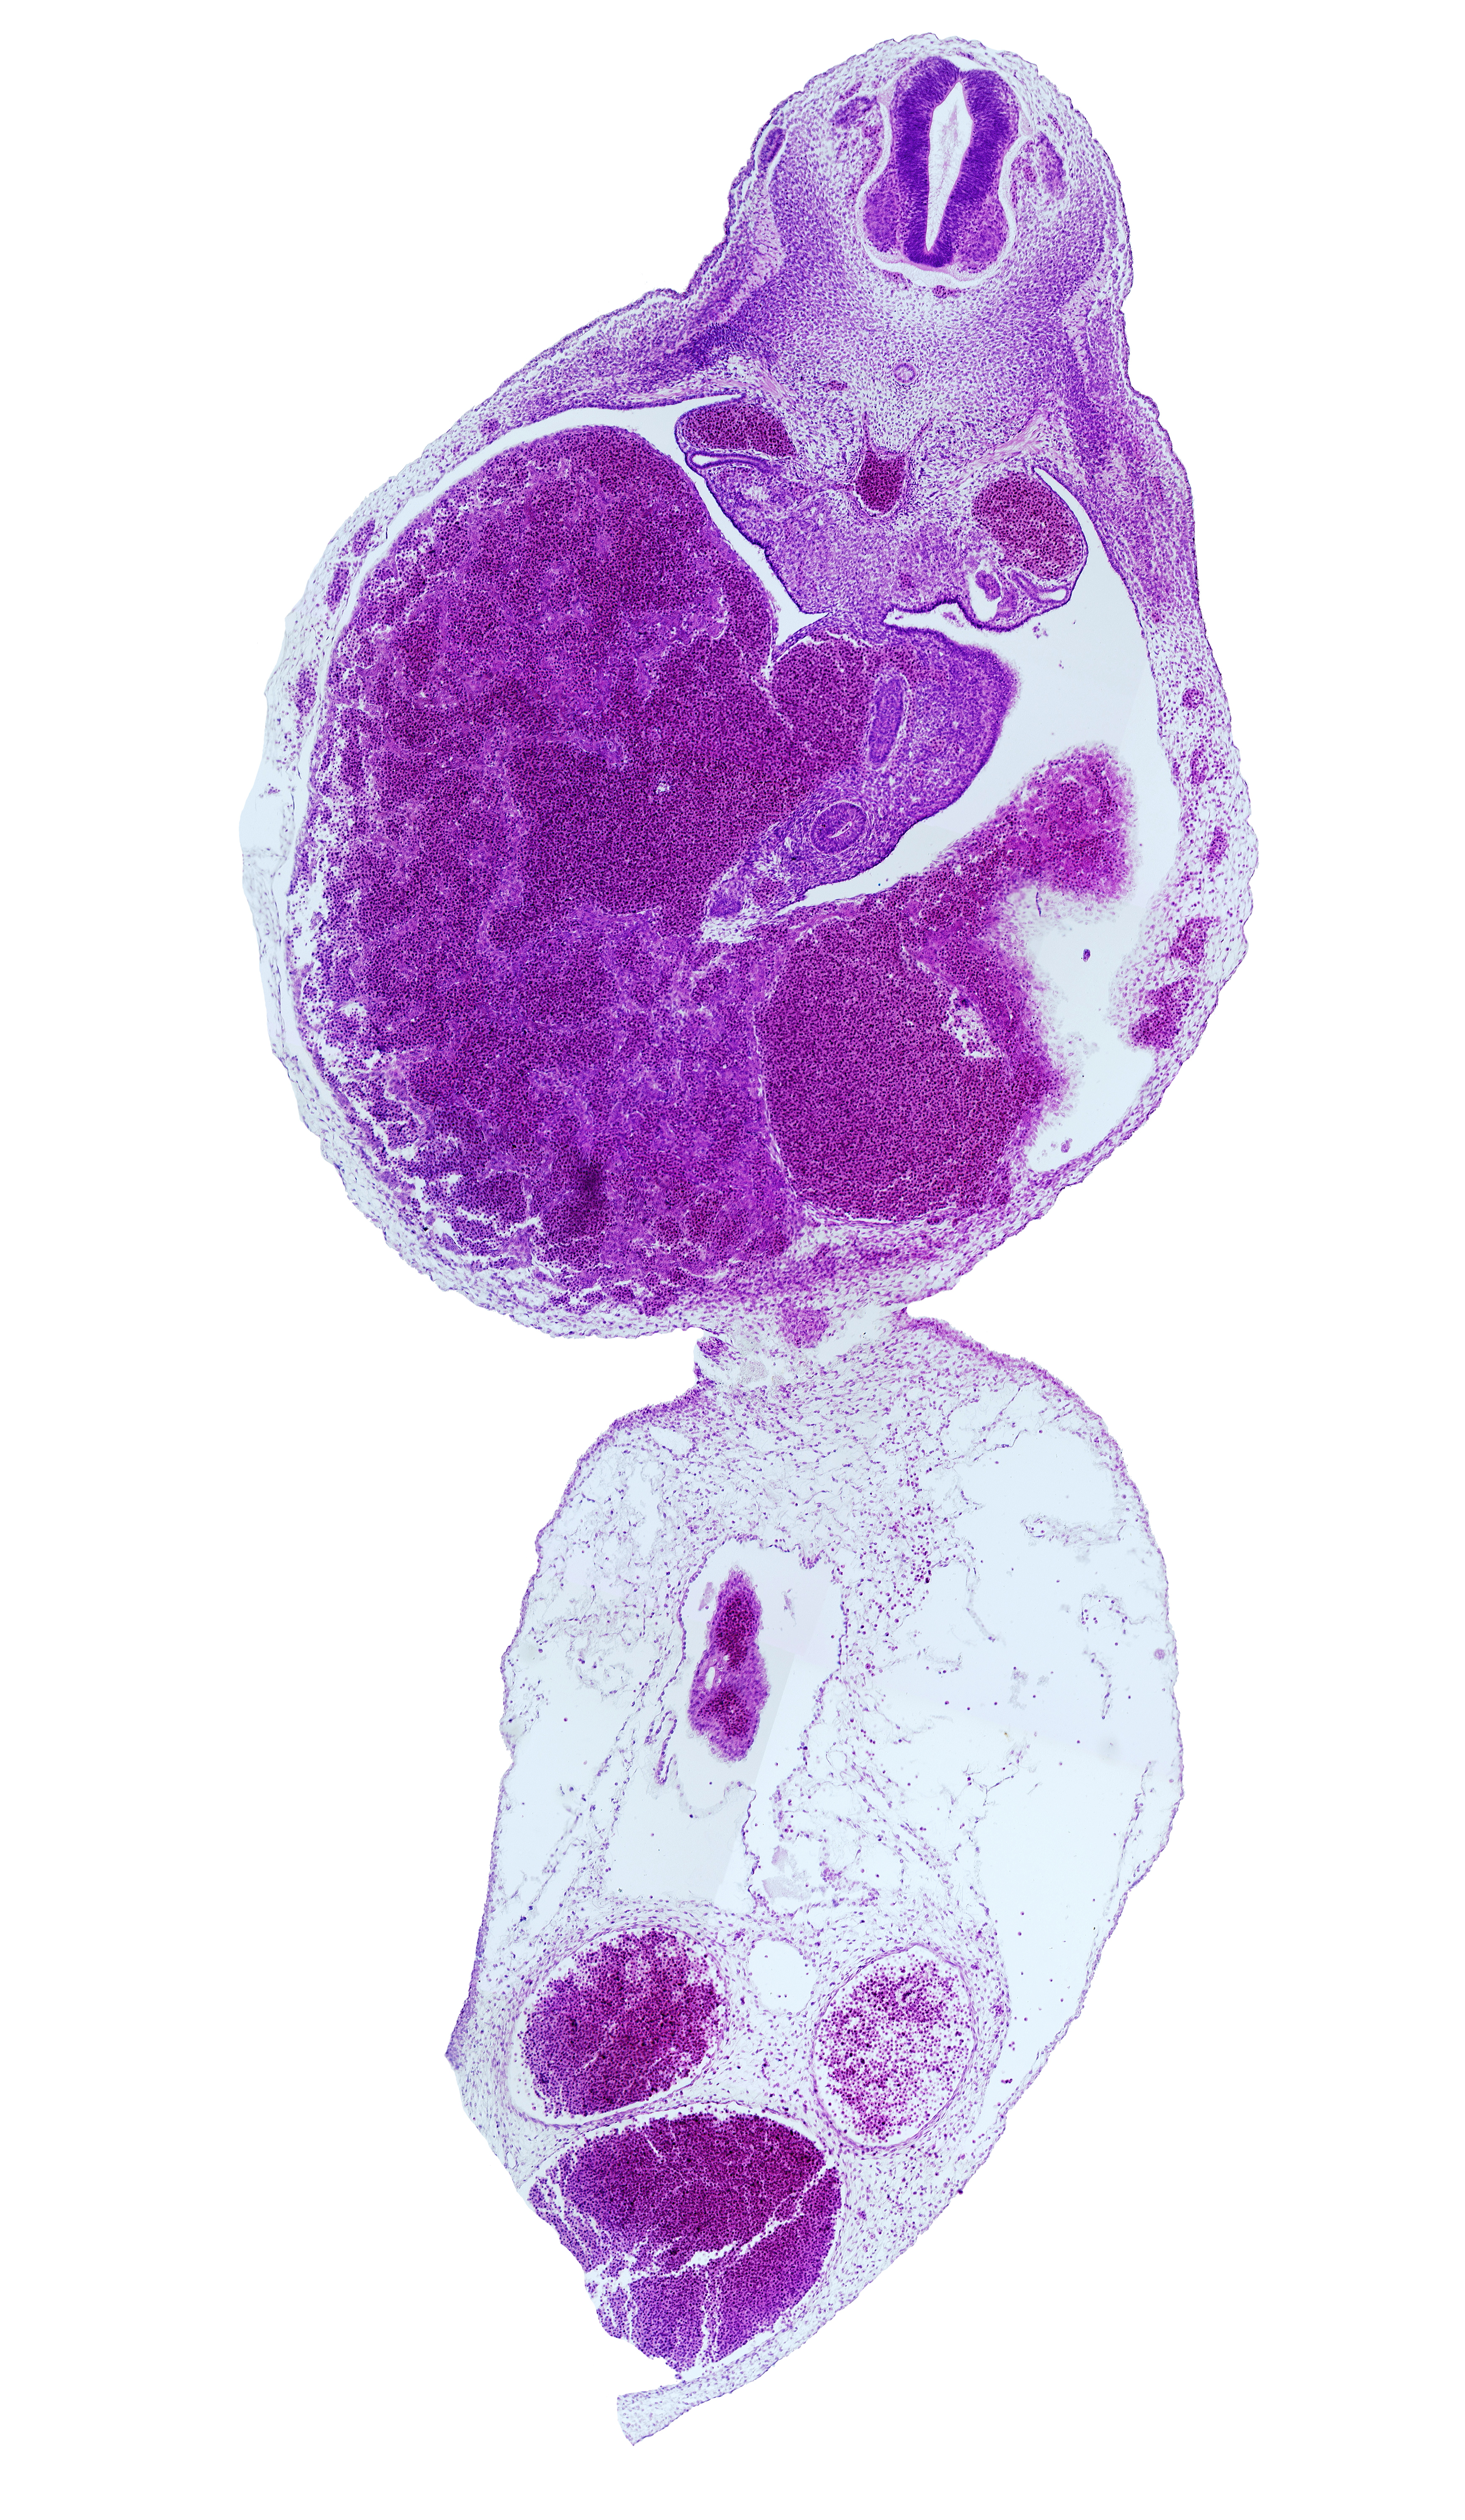

Carnegie Embryo #721 | Location: 17-03-05

Keywords: allantois, dorsal pancreatic bud, ductus venosus, duodenum, epaxial part of myotome, hypaxial part of myotome, left umbilical artery, liver, mesonephric duct, neural arch blastema, postcardinal vein, rib blastema, right umbilical artery, subcardinal vein, umbilical coelom, umbilical vein, umbilical vesicle stalk remnant

Source: The Virtual Human Embryo.